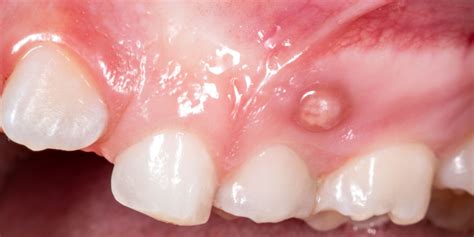

Llamamos fístula dental al canal que se origina desde la zona infectada de un diente hasta la superficie exterior de la encía. En ese canal se acaba depositando pus y, conforme se llena, se crea una protuberancia o grano próximo a las encías. Una fístula dental es una pequeña abertura o canal anormal que se forma en la encía o en la región cercana a la raíz de un diente infectado. El pasaje actúa como depósito de pus y a medida que se llena, se forma una pequeña protuberancia en forma de grano cerca de las encías.

La fístula al aparecer se presenta normalmente en la encía, en la cima superior del diente. Se trata, como bien indicábamos, de un bulto con pus producido por diferentes razones. Al principio, las encías se inflaman ligeramente y enrojecen. Con el tiempo, la fístula dental se llena de pus y aparece un dolor punzante. Si se aplica mucha presión, el pus drena hacia la cavidad oral. Cuando se forma la fístula dental, aún no causa dolor. Al principio, la zona afectada se hincha. Las encías se enrojecen y hay una sensación de tensión en el diente. A continuación, se forma una ampolla en la encía, encima o debajo del diente afectado, que se llena de pus a medida que avanza. La fístula dental empieza a palpitar y doler. Puede que incluso se te hinche la cara del lado afectado y te duela la cabeza.

- Abscesos dentales: La presencia de una fístula dental puede dar lugar a la formación de abscesos dentales. Un absceso dental es una acumulación de pus causada por una infección bacteriana en el tejido dental. En el caso de una fístula dental, el absceso puede manifestarse como una protuberancia roja y dolorosa en las encías cerca del diente afectado. Esta protuberancia puede estar acompañada de sensibilidad al tacto y al calor, así como de hinchazón en el área circundante.